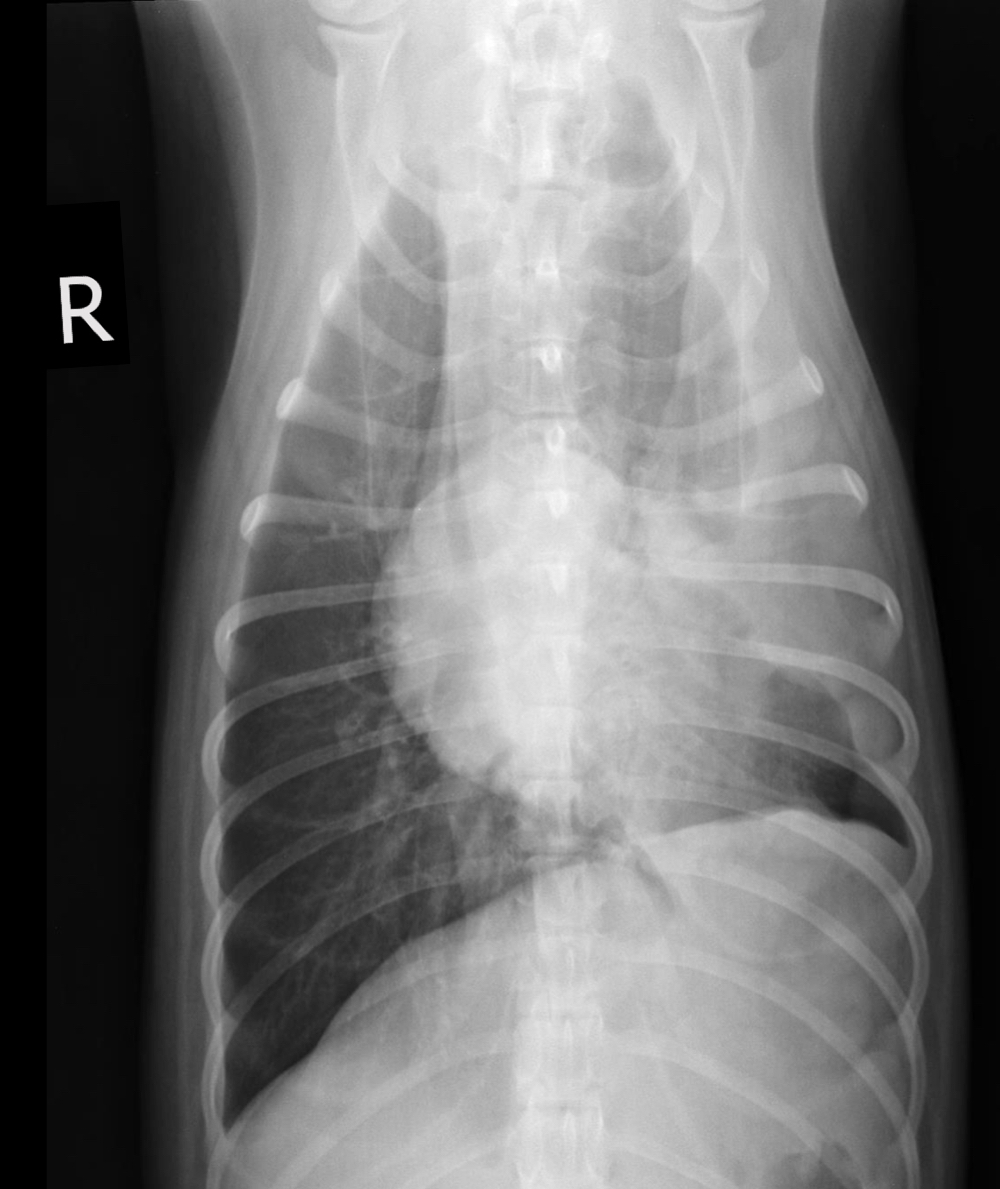

Q

What is likely happening in this radiograph?

A

• large soft tissue mass - opacity extends into thorax

• rib lesions

• mass displaces cardiac silhouette to the left